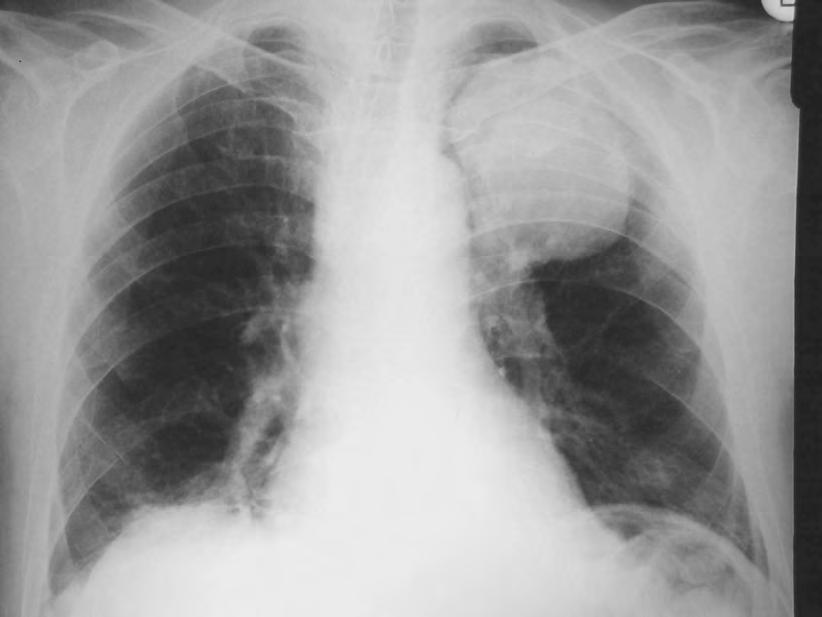

Expanzivní ložisko vCNS může být někdy způsobeno benigním patologickým procesem (abscesem, kavernomem, meningeomem), ale může jít také ometastázu známého nebo doposud ukrytého tumoru, viz obr. 1.4 a1.5. Do mozku často metastazují následující tumory: bronchogenní karcinom, obzvláště jeho malobuněčná varianta, karcinomy prsu aledvin. V80 %případů jsou tyto metastázy uloženy supratentoriálně.

Obr. 1.4 Miliární metastázy mozku bronchogenního karcinomu s okluzí aquaeduktu a hydrocefalem. MR zobrazení v koronárním řezu v T1 váženém čase po aplikaci kontrastní látky i.v. Bílá šipka ukazuje v tektu umístěnou metastázu blokující svou expanzí aquaedukt.

Metastázy mohou vCNS vytvořit jak solitární, tak ivícečetná ložiska, mohou však také infiltrovat meningy (bronchogenní karcinom, karcinomy prsu ižaludku).

Nález multiformního glioblastomu se při CT vyšetření zobrazuje jako hypodenzní ložisko s často vyjádřeným mass-efektem. Po nitrožilním podání kontrastní látky se uvíce než 90%nemocných zobrazuje hyperdenzní prstenec, tzv. ring sign Tento nález není typický jen pro glioblastom, ale je možno se sním setkat iumozkového abscesu. Podobně jako glioblastom může hypodenzní ložisko vCT obraze vytvořit rovněž metastatický nádor nebo infarkt mozku. Edém obklopující glioblastom je rozsáhlý amá nepravidelný prstovitý charakter. Po podání kontrastní látky se nasycení (enhancement) nevytvoří u60 %nízkostupňových astrocytomů, 30 %anaplastických astrocytomů, ale pouze

Obr. 1.5 Miliární metastázy mozku bronchogenního karcinomu s okluzí aquaeduktu a hydrocefalem. MR zobrazení v sagitálním řezu v T1 váženém čase po aplikaci kontrastní látky i.v. Bílá šipka ukazuje v tektu umístěnou metastázu blokující svou expanzí aquaedukt.

u6,5%glioblastomů. Platí, že čím vyšší je malignita, tím větší je imass-efekt.